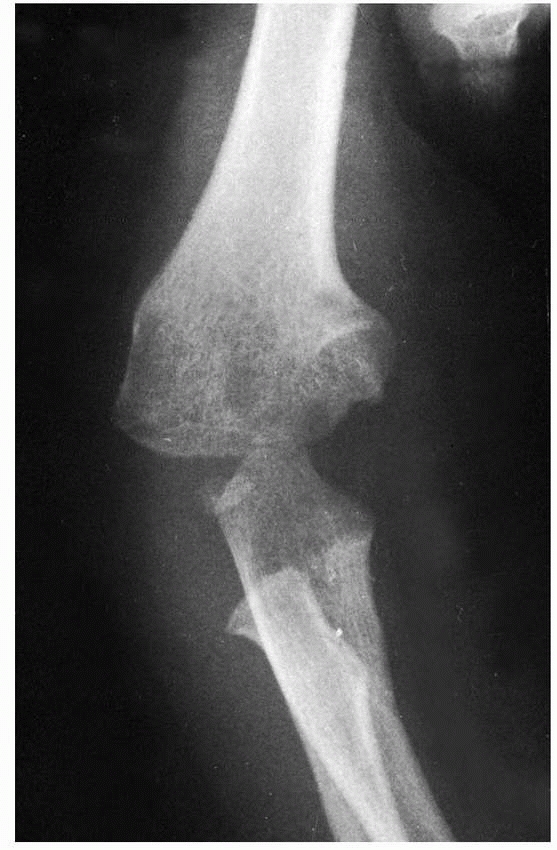

and is most commonly associated with the extensive dissection necessary

to effect a late reduction or from loss of the blood supply at the time

of injury.73,85,113 Wilson,201

much like Legg-Calveé-Perthes disease in the hip. Any residual deformity is usually related to loss of motion.

![]() |

FIGURE 15-23

Osteonecrosis and nonunion developed in this child after extensive dissection and difficulty in obtaining a primary open reduction. A. Injury film. B. Two years later, there was extensive bone loss in the metaphysis and a nonunion of the condyle. |